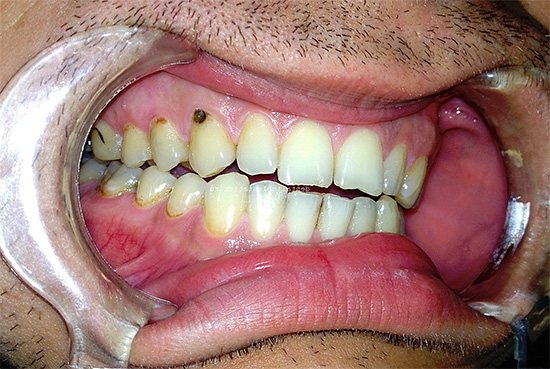

Фото: средняя и глубокая стадии